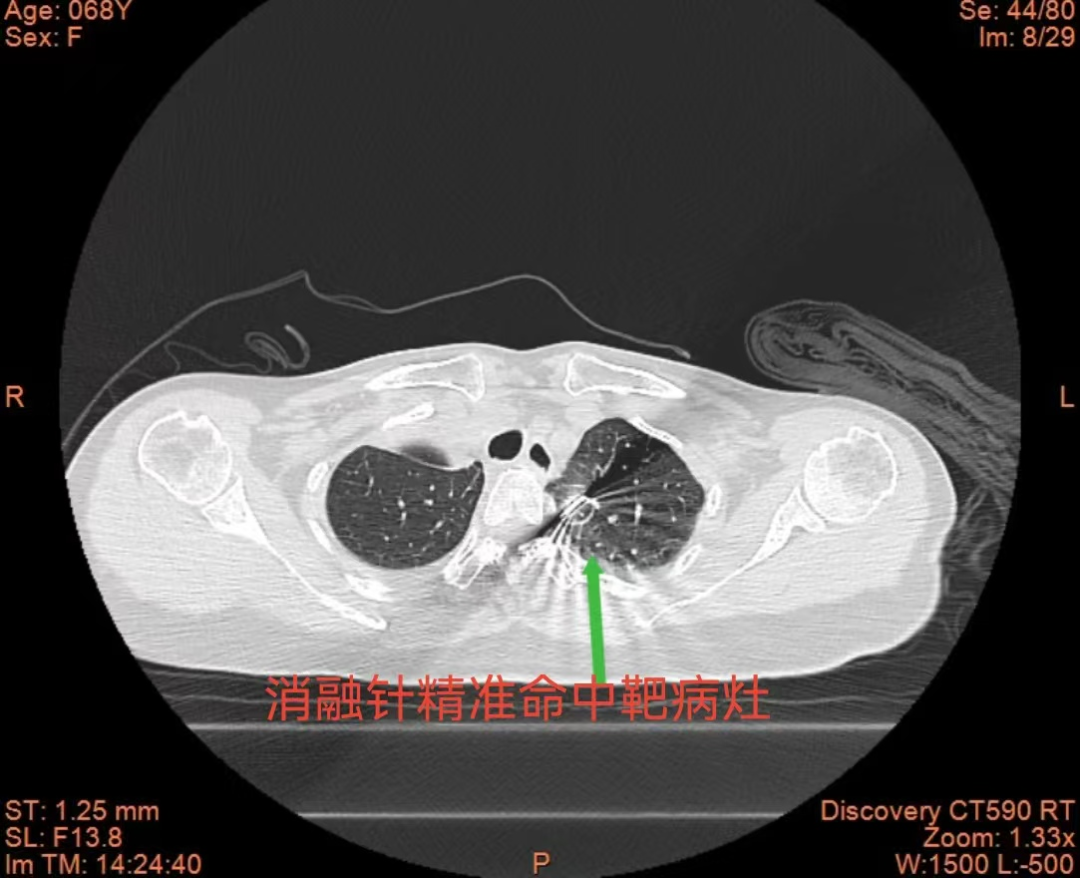

術(shù)中,團隊在CT精準(zhǔn)導(dǎo)航下,先向左側(cè)胸腔緩慢注入空氣,構(gòu)建人工氣胸,在左上肺結(jié)節(jié)與主動脈弓之間形成安全空氣隔離帶,同時配合液體隔離技術(shù),有效減輕術(shù)中疼痛。憑借精準(zhǔn)的穿刺技巧與術(shù)中的嚴(yán)密監(jiān)測,消融針精準(zhǔn)抵達(dá)病灶,手術(shù)順利完成,目前患者已康復(fù)出院。